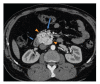

Paragangliomas are extra-adrenal tumors of the autonomic nervous system and may be found within the skull base, neck, chest, and abdomen. When presenting within the abdominal cavity, they may arise as a primary retroperitoneal neoplasm and can mimic vascular malformations or other conditions related to specific retroperitoneal organs such as the pancreas, kidneys, or adrenals. Retroperitoneal paragangliomas are mostly benign with good prognosis; however, they can present with abdominal pain, palpable mass, or hypertensive episodes. Patients should be initially evaluated with catecholamine levels, followed by computed tomography or magnetic resonance imaging to locate the primary lesion. Surgical excision remains the mainstay of treatment, although advanced disease and proximity to vital organs can make excision difficult or impossible. This case report describes a patient who initially underwent work up for a suspected pancreatic head mass which was discovered to be a retroperitoneal paraganglioma by frozen section.